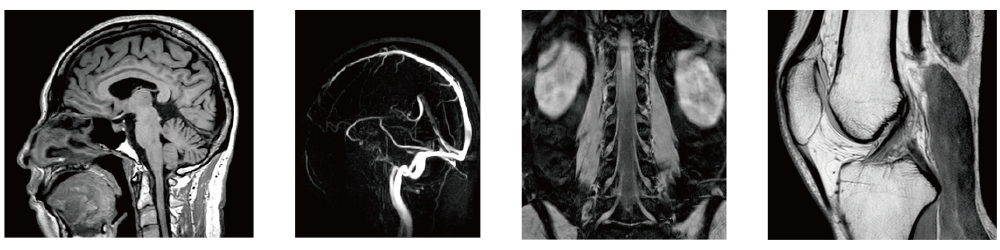

画質を維持しながら撮像時間を短縮するIP-RAPIDと、開発にDeep Learning技術を活用し*8、高画質化を図るDLR Plus。2つの技術の組み合わせにより、診やすい画像を高速で得られます。

IP-RAPID×DLR Plusは撮像時間の短縮も可能なため、同一検査時間であれば、より多くの撮像が可能となります。従来検査に対して、異なる画像種類や断面など、追加撮像によって情報量を増やすことができ、診断をより確かなものに。

IP-RAPID×DLR PlusはVolumeScanやRadialScan、HalfScanといった基本撮像に加え、MultiContrastScanのFatSepやDWIなど多くの撮像法でお使いいただけます。広範囲DWIやWhole Spine撮像など時間のかかるWide Scanにも併用でき、多くの部位で従来よりも詳細な情報を得ることができます。

AutoPose Cardiac GUI

AutoPose FemalePelvis

AutoPose Knee

スライスライン設定サポート機能"AutoPose"は、Scanogram撮像終了と同時にスライスラインを設定します。

MRA撮像終了後、自動で頭部MRAのクリッピングを実行します。自動クリッピングは、頭部の特徴量に基づいて抽出範囲を識別します。自動クリッピング処理後の画像に対し、追加のクリッピングを行うことも可能です。